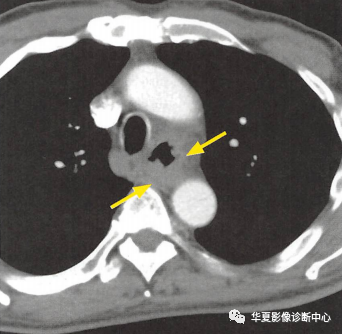

(上圖:增強(qiáng)CT食管壁不規(guī)則增厚)

①食管壁改變:食管壁全周環(huán)形或局部不規(guī)則增厚,相應(yīng)平面管腔變窄或消失,呈腫塊樣改變;

②食管周?chē)鹃g隙模糊、消失:提示食管癌向外侵犯;

③周?chē)M織器官受累:多為氣管和支氣管,常形成食管-氣管瘺,其次可侵犯心包膜、左心房和主動(dòng)脈等;

④轉(zhuǎn)移:以縱隔、肺門(mén)及頸部淋巴結(jié)轉(zhuǎn)移多見(jiàn),也可逆行性轉(zhuǎn)移至上腹部淋巴結(jié),少見(jiàn)肺轉(zhuǎn)移。CT增強(qiáng)掃描可見(jiàn)瘤體輕度強(qiáng)化。較大瘤體呈不均勻強(qiáng)化,常合并低密度的壞死灶,較小瘤體強(qiáng)化均勻。

下段食管癌CT圖像

下段食管腔消失,呈腫塊樣改變,平掃呈等密度,增強(qiáng)后有明顯強(qiáng)化